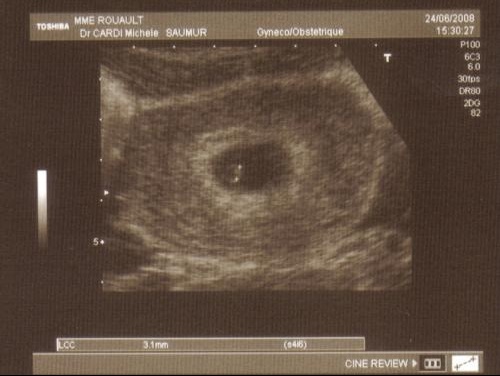

15042012 à 18h45. Je dois prendre PROGESTAN a mettre dans le vagin pendant 15 JOURS. Je suis enceinte de 4 semaines et jai fait ma 1ère écho ce matin.